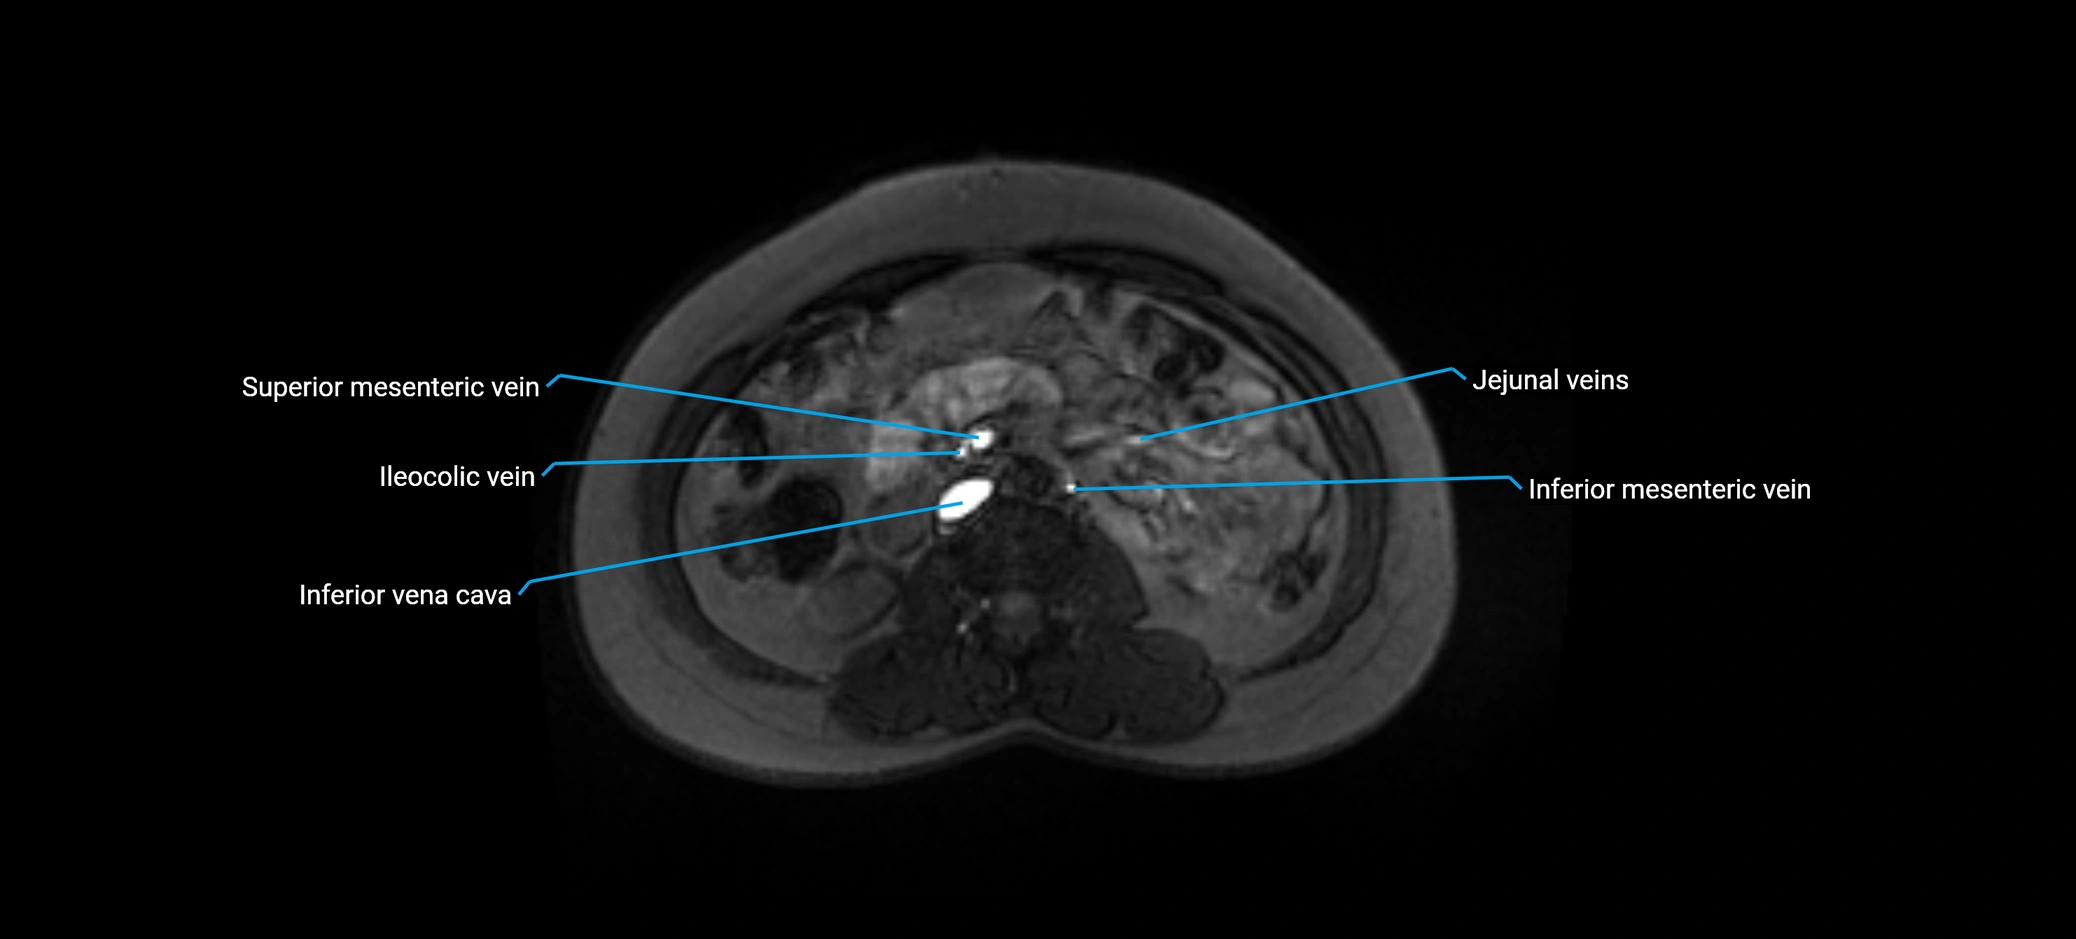

MRI image

image